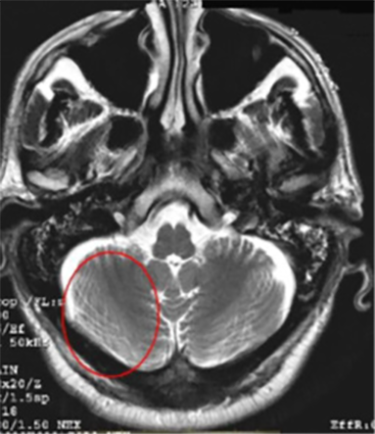

| DWI/DTI Ring Ring-like artifact | ![]() | Intense orbit signal |